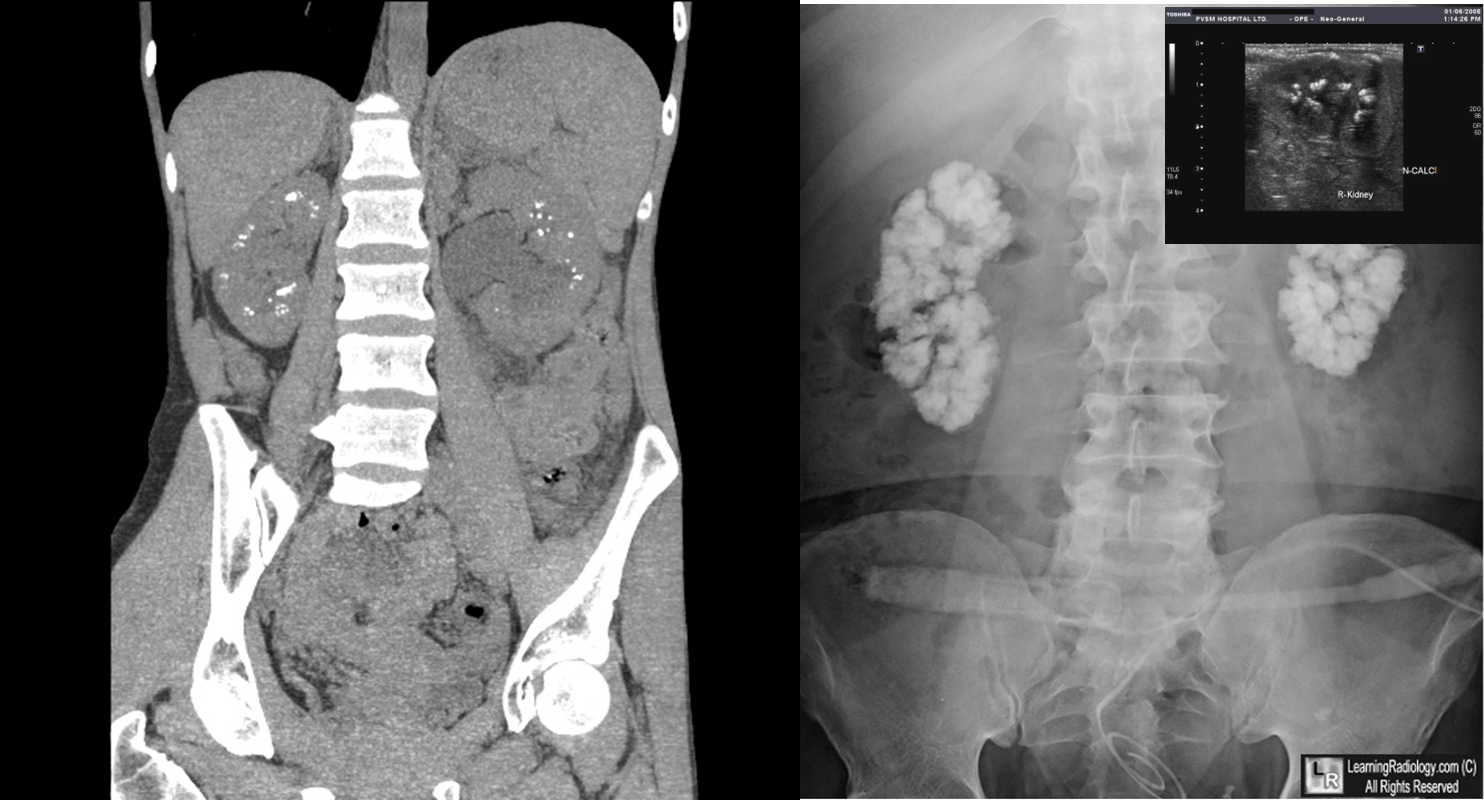

Deposits of calcium in the kidneys parenchyma.

A.Cortical B. Medullary. This type is more common. The commonest causes are - Hyperparathyroidism - Renal tubular acidosis - Medullary sponge kidneys